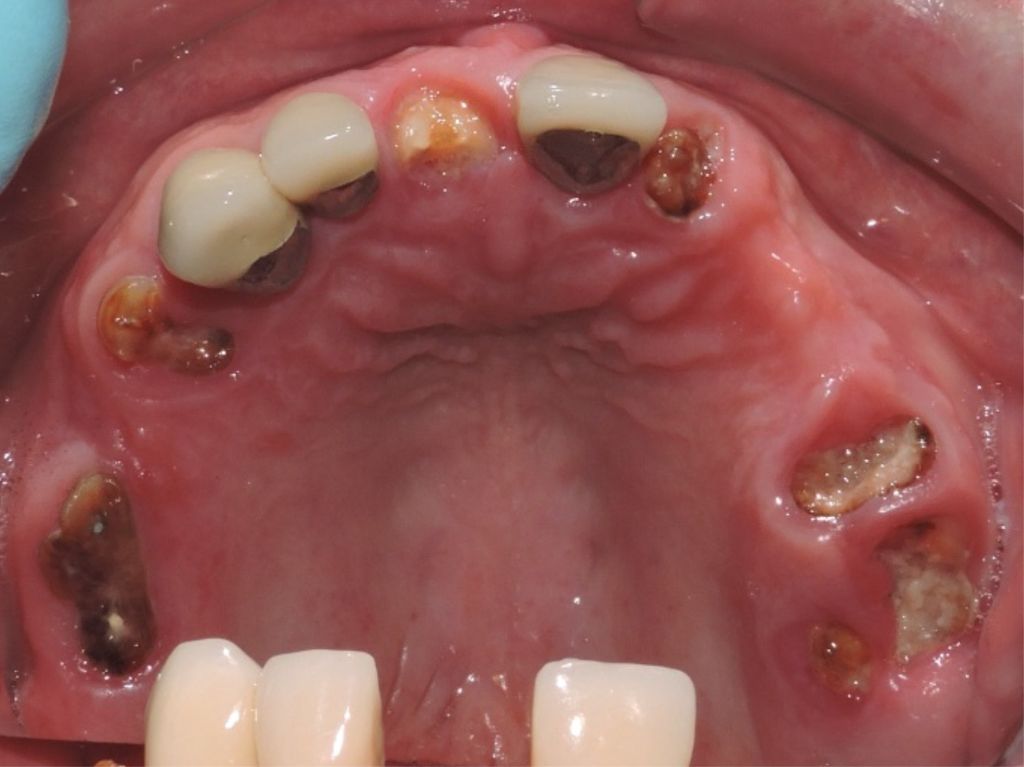

Before